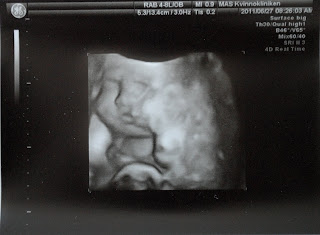

Bebisen v. 33

Nu väger bebisen c:a 2 kg och mäter totalt omkring 45 cm från topp till tå.

Förutom att gråta så kan nu bebisen göra allt som en nyfödd 40 veckors bebis kan. Det börjar bli trångt om utrymme inne i livmodern, men bebisen kan fortfarande sparka och röra sig. Den sover mycket under den här perioden, precis som en nyfödd bebis. Ögonen rör sig under REM-sömnen, och forskarna tror att fostret drömmer livfullt inne i livmodern.